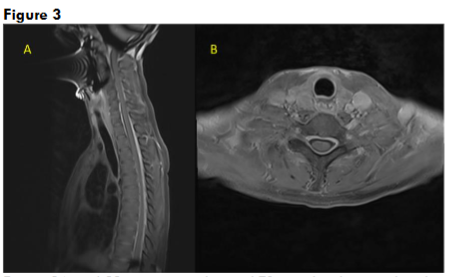

Her routine blood investigations including blood counts, liver and renal function tests were normal. Serum vitamin D and vitamin B12 levels were normal. CT brain and CT cerebral angiography was done in emergency to rule out any pituitary apoplexy, subarachnoid hemorrhage, vascular aneurysm, or vascular malformation, which was normal. Gadolinium-enhanced magnetic resonance imaging (MRI) showed bilateral subdural effusion, with diffuse smooth pachymeningeal enhancement (Figure 1). There was drooping of splenium of corpus callosum, sagging of the midbrain, reduced mammillo-pontine distance, and pituitary hyperaemia. MRI of the spine showed smooth dural enhancement of the cervical and thoracic region. No CSF leak was noted in the contrast images. MR venogram showed engorgement of the venous sinuses. The imaging findings were in countenance with SIH (Figure 2). Ultrasound of the thyroid showed mild diffuse thyroid enlargement, with mild increase in vascularity.